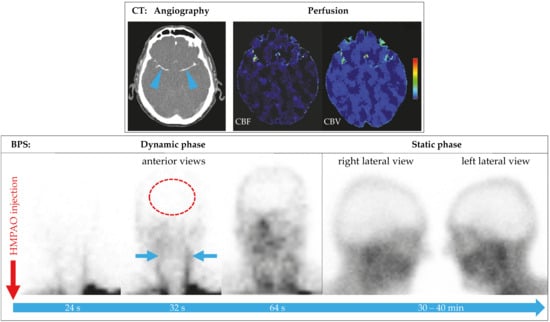

4.4. BPS in Patients on vaECMO or LVAD